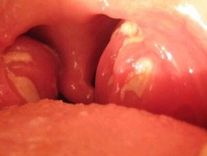

- Boğaz İltihabı

- Bademcik Hastalığı